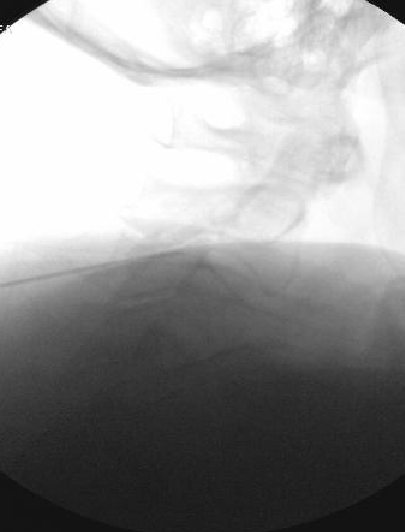

Nasty neuritis. This is 80 degrees 90 seconds.

These images look great. Sorry it happened? Steroid?

Lyrica Rx sent in, and we're starting it for chronic pain (and neuritis). She gets a shoulder scope in two weeks for a large RCT. I like antineuropathics (gabapentin 100mg HS or BID) perioperatively in general. I wish they were given 2 weeks before and after ALL orthopedic surgeries.

Dexamethasone given before RFA needles were removed.